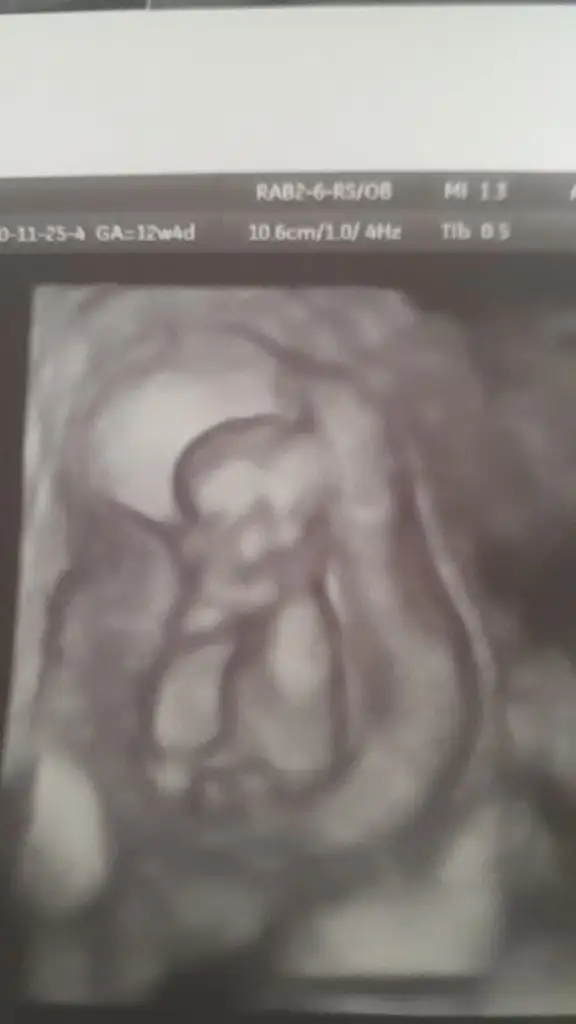

Erkek gibiMerhabalar bana da tahmin yaparmisiniz acaba

Buna da bakabilirmisinizKız gibi boş görünüyor bacak arası en iyi 11 12 13 haftalar olmalı

Orda bi pipi var sanki12+0 cinsiyet hakkında yardımcı olabilir misiniz.kırmızıyla çizdiğim resim videodan üstten bacak arası videodan ekran görüntüsü..

Karşıya bakıyor başka USG varmı diklik belli olmuyor %60 derim erkek ama emin değilim12+0 cinsiyet hakkında yardımcı olabilir misiniz.kırmızıyla çizdiğim resim videodan üstten bacak arası videodan ekran görüntüsü..

Ikra meyra canım doktordan geliyorum. Sen haklı çıktın Doktor başta kıza benzetti kordon vardı diye sonra biraz incelemeden sonra da erkeğe benzetti %80 erkek dedi. Tabi 3 hafta sonra tam detaylıda daha net görürüz dedi. Bundan sonra değişir mi ki bilemiyorum